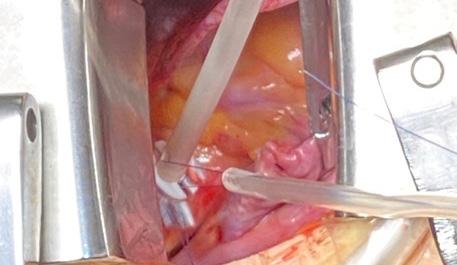

Minitoracotomia dreaptă

Pacientul este plasat în decubit dorsal cu umărul drept ușor ridicat; este anestezi at și intubat cu sondă dublu lumen care să permită ventilația selectivă pulmonară. Se introduce o sondă de ecocardiografie tran sesofagiană (ETE) cu ajutorul căreia se confirmă diagnosticul preoperator și me canismul patologiei mitrale, se ghidează canularea periferică pentru circulație ex tracorporală (CEC) și se evaluează funcția cadiacă și calitatea gestului asupra VMi. Pacientul este rotat 30 grade către stânga, efectuându-se o toracotomie antero-la terală de 5-7 cm în al IV-lea spațiu inter costal. Rotirea pacientului către stânga nu este obligatorie, multe centre renunțând la această abordare, din cauză că inima se îndepărtează de toracele drept. În schimb, este important ca brațul drept să fie flectat la 120 grade și în ușoară abducție, pentru a se îndepărta de viitoarea incizie (Fig.1,2).

Hemostaza minuțioasă la nivelul pere telui toracic este esențială. După efectuarea toracotomiei, se folosește un depărtător de

tip “Alexis soft tissue retractor”, dublat de un depărtător standard dacă se folosește tehnica vizualizării directe (Fig.3). Managementul chirurgical al circulației extracorporale

După atingerea ACT-ului standard, mai mare de 480 secunde, se pornește CEC. Se preferă abordarea prin care se golește mai întâi cordul, urmată de inci zia pericardului la 2-3 cm superior de nervul frenic drept și suspensia acestuia, pentru a nu leza cordul în cursul acestor manevre (Fig.10).

Disecția completă cu electrocauterul a șanțului interatrial este un aspect critic în expunerea VMi. Aceasta se efectuează până la nivelul fossei ovalis, aducând chi rurgul foarte aproape de VMi, chiar și în situații anatomice dificile (Fig.11).

În continuare, se efectuează două bur se la nivelul aortei ascendente, sprijinite pe petece, pentru canula de cardioplegie anterogradă. Este important de mențio nat că efectuarea bursei de cardioplegie și introducerea canulei trebuie să se facă după inițierea CEC și golirea cordului, facilitând astfel expunerea aortei ascen dente și evitând lezarea urechiușei drepte (Fig.12).

Urmează clamparea aortei ascenden te, care se realizează prin contraincizie în cazul clampului Chitwood (Fig.14).

După terminarea cardioplegiei și ob ținerea asistolei, se incizează atriul stâng la nivelul șanțului interatrial disecat și se montează un aspirator intraatrial (Fig.13).

De îndată ce expunerea valvei mitrale este obținută cu ajutorul unui depărtă tor auto-static, se începe inspecția valvei (Fig.14).

În concluzie, abordul minim invaziv al valvei mitrale prin minitoracotomie dreaptă, folosind tehnica vizualizării di recte, oferă o vizualizare excelentă a aces teia. Urmând pașii simpli descriși mai sus, valva mitrală poate fi expusă corect, facil și fără incidente, urmând apoi pașii clasici ai plastiei/protezării acesteia.